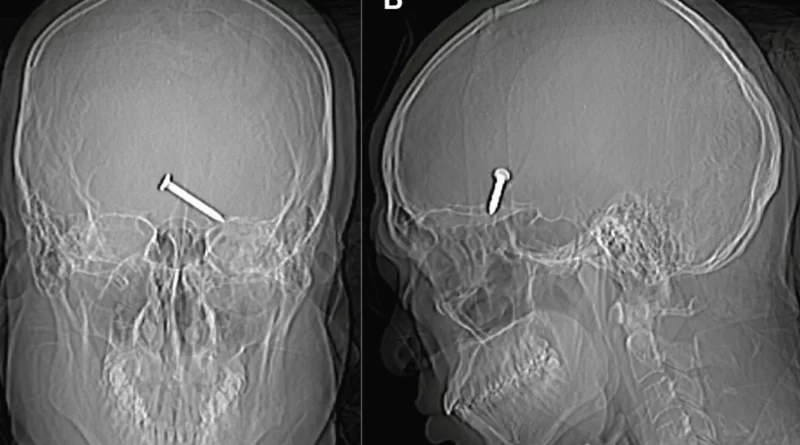

Um raio-x do crânio mostrou que o prego de três centímetros havia se alojado no cérebro do malasiano. Parte do crânio dele foi dilacerada pelo impacto. Apesar da gravidade do ferimento, o homem apresentava bons sinais vitais.